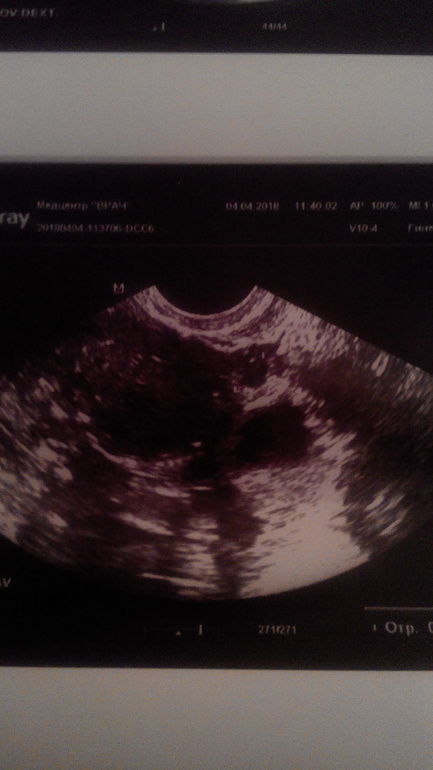

2-го апреля ХГЧ 1200,03.04 на УЗИ пусто, 04.04 была на УЗИ дважды .Одна узистка видит ПЯ в трубе 8мм, а в другом мед.центре смотрели 2 врача на двух разных аппаратах и не увидели НИЧЕГО!!!

По своему фото я тоже ничего не понимаю...

А трапециевидное затемнённые контуры вокруг это матка. У меня всегда смотрят отдельно матку, отдельно яичники. Пусть вам также посмотрят

Я так понимаю, на вашем фото ПЯ и в нем ЖМ?Если это так, то почему в моем нет?